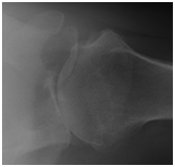

Shoulder replacement shoulder replacement

X-ray of shoulder showing a surface replacement